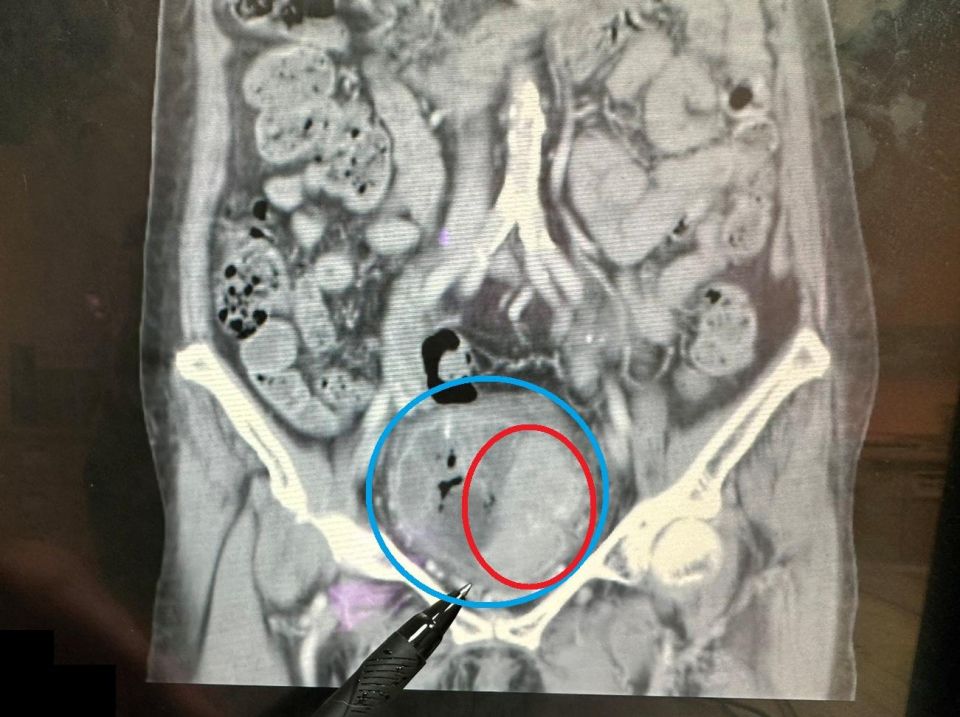

(記者鍾盛增/苗栗報導)76歲的陳女士因近一個月持續出現無痛性血尿症狀,而到醫院就醫。經醫師檢查發現,她雖然有明顯的血尿狀況,但未出現發炎反應、尿路結石、腎水腫或腎腫瘤的情況,且腎功能正常。進一步安排靜脈注射腎盂攝影,顯示在膀胱內有大片陰影,續以膀胱鏡檢查,發現膀胱內有一個約7x6公分的巨大腫瘤。所幸,經醫師安排「經尿道膀胱腫瘤刮除手術」後,順利清除腫瘤,也成功保留膀胱,目前恢復良好並定期回診追蹤。

大千綜合醫院泌尿科醫師陸兆明表示,此位病人的膀胱腫瘤體積頗大,已佔據未漲尿時的膀胱將近1/2空間,但因為腫瘤細胞尚未侵犯到膀胱外圍,也沒有骨盆淋巴結轉移的情況,因此適用「經尿道膀胱腫瘤刮除手術」來處理腫瘤。此手術透過膀胱內視鏡,由尿道進入膀胱來逐步刮除腫瘤,不僅可得到足夠的檢體,來檢查癌細胞有無侵犯深層肌肉,並將肉眼可見的病灶加以切除。